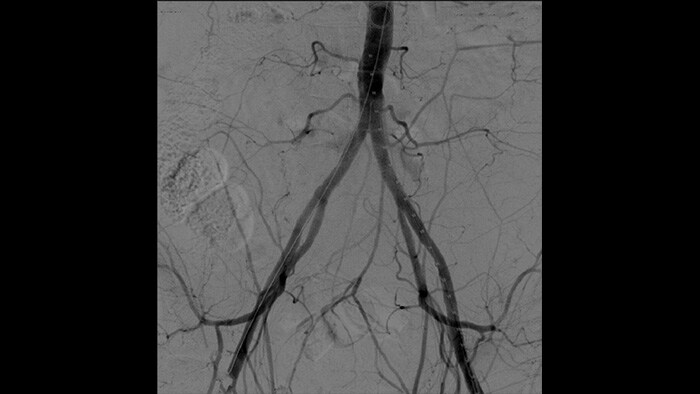

With the Philips Zenition mobile C-arm, Dr. Vila is obtaining outstanding high-quality images that allow him to perform most vascular procedures at the low dose setting.

With the Zenition, our DSA image quality has improved greatly. We no longer see a grainy image. We just see a very clear image."

Digital subtraction angiography (DSA) is used in interventional vascular procedures to clearly visualise blood vessels by removing structures that can obscure vessel visibility. Roadmap fluoroscopy overlays a previously acquired subtracted contrast image on the live fluoroscopy, allowing you to track a device without reinjecting contrast.